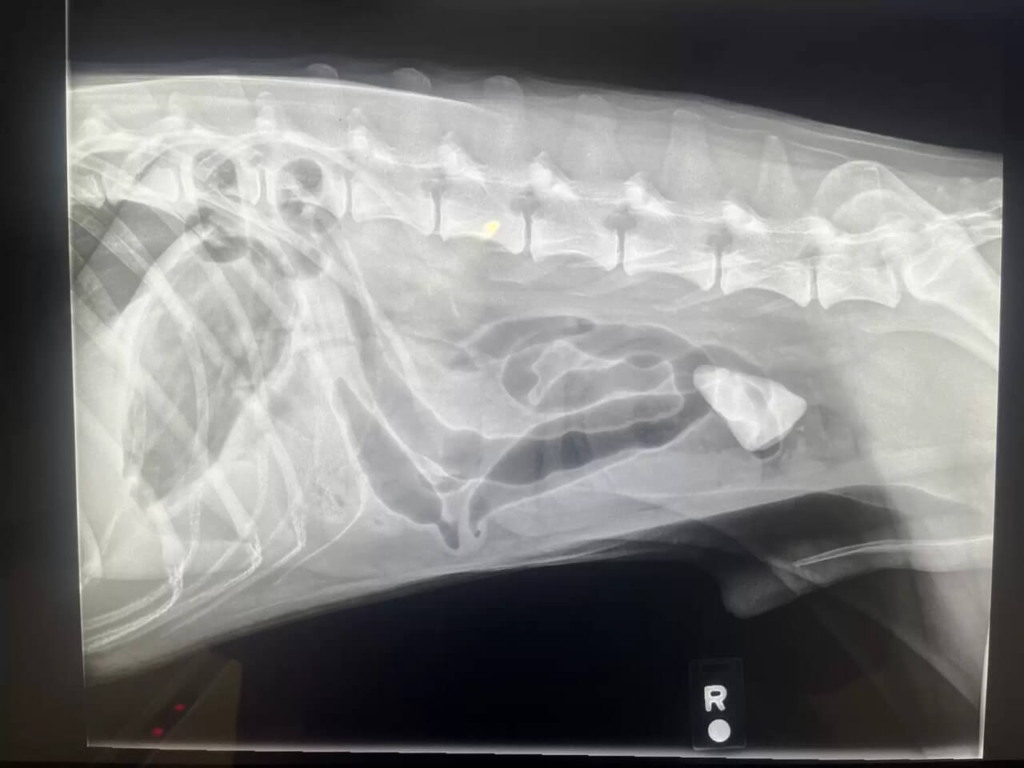

A tutora de Denali levou o cachorro até a clínica porque ele não estava comendo. Em um raio-X, descobriram a pedra no estômago. Depois de um dia inteiro no veterinário, o cachorro não estava melhorando. Então a Dra. Sharpe, veterinária responsável pela clínica, determinou a necessidade de uma cirurgia para remover a pedra.